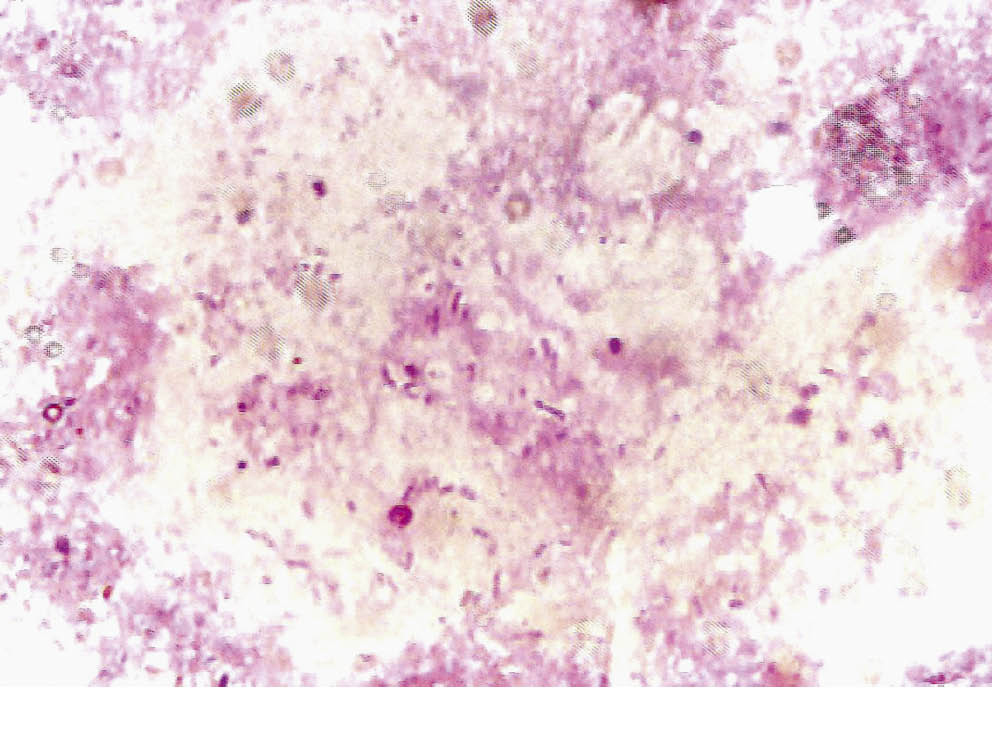

При бактериоскопическом исследовании в скарификатах кожи обнаружены гомогенные кислотоустойчивые палочки (рис. 2), бактериоскопический индекс (БИН) 1+, в соскобе со слизистой поверхности носа кислотоустойчивые палочки не обнаружены.

Рис. 2. Кислотоустойчивые палочки в мазке, окрашенном по методу Циля — Нильсена / Fig. 2. Acid-resistant bacilli in a smear stained according to the Ziehl — Neelsen method